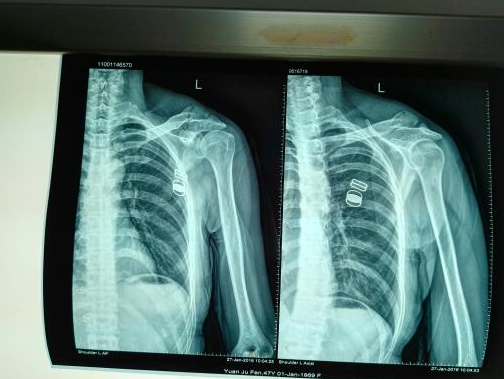

杭州尊龙凯时科技:专业解决肱骨大结节骨折,3D打印与CT重建

肱骨大结节骨折是一种较为常见的骨折类型,常爆发在运动损伤、交通事故等情况下。古板的手术要领虽然能够解决问题,但…